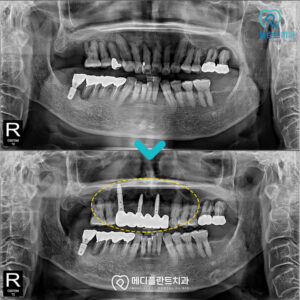

춘천수면임플란트 의식하진정으로 편안하게! 안녕하세요:) 춘천수면임플란트치과 메디플란트치과입니다. 유치가 빠지고 새롭게 자라나는 영구치는 말 그대로 평생 사용해야 하는 치아이기 때문에 한 번 상실하면 다시 자연적으로 회복되기 어렵습니다. 따라서…